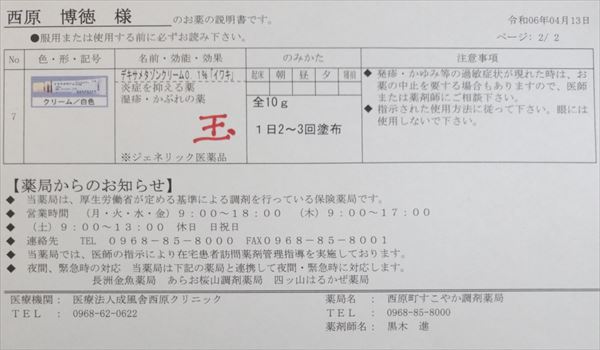

2024.4.13 オロパタジンに戻る